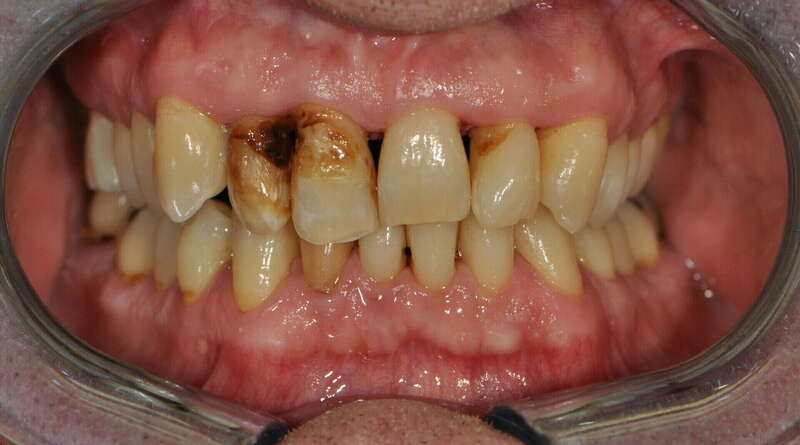

3. Restaurations par couronnes céramo-céramiques.